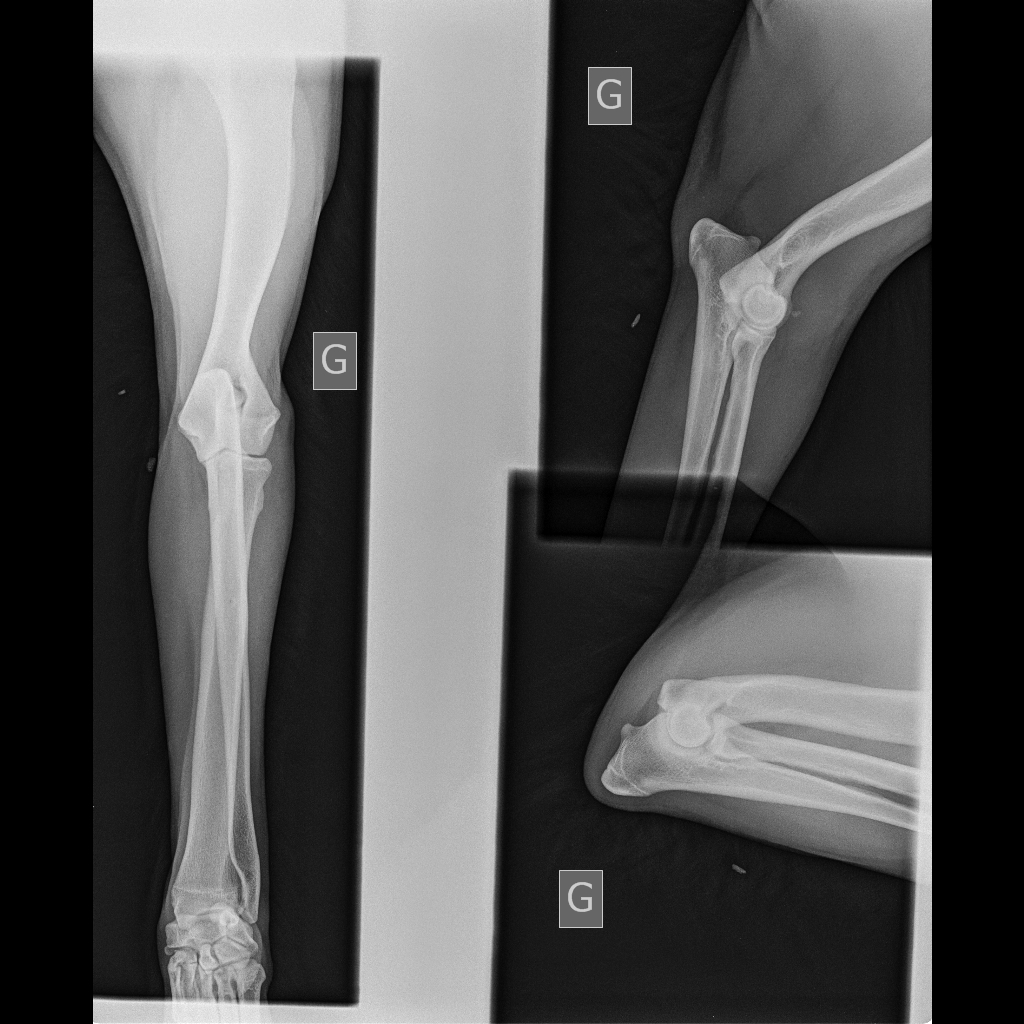

Télécharger radio eragone d'ainhoa coude

radio eragone d'ainhoa coude

radio des coudes de eragone

Télécharger radio eragone d'ainhoa coude 2

radio eragone d'ainhoa coude 2

radios des coudes de era